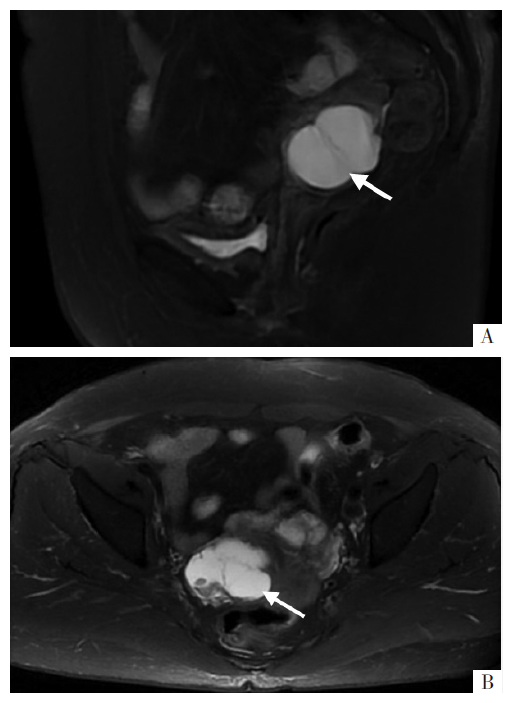

阔韧带子宫内膜样癌是罕见的特殊部位的恶性肿瘤。其发病率极低,疾病的机制、诊断和治疗尚未明确。其临床表现缺乏特异性,术前常误诊为子宫或卵巢肿瘤。报告1例65岁阔韧带子宫内膜样癌患者的诊疗经过,术前误诊为卵巢肿瘤,经手术探查和术后病理明确诊断,另行全面分期手术。术后随访7个月,病情稳定,影像学检查未见异常,肿瘤相关指标未见异常。对于妇科检查扪及附件区肿物固定,影像学提示肿物边界清楚,需要考虑阔韧带肿瘤可能,应尽早手术。经病理诊断为阔韧带恶性肿瘤,应及时全面分期手术,术后长期随访。

Endometrioid carcinoma of the broad ligament is a rare malignant tumor in a specific site. Due to its low incidence rate, the mechanism, diagnosis and treatment have not been clarified. The clinical manifestations lack specificity and it is often misdiagnosed as uterine or ovarian tumors before surgery. Therefore, this paper reports the diagnosis and treatment of a 65-year-old patient with broad ligament endometrioid carcinoma. Preoperatively, the patient was misdiagnosed as an ovarian tumor, but the diagnosis was confirmed through surgical exploration and postoperative pathology. The patient underwent a second surgery which was a comprehensive staging. Currently followed up for seven months,the patient recovered well, and showed no abnormalities in imaging examination and normal tumor indicators. With retrospective analysis of this case, when gynecological examination revealed the fixation of the tumor in the adnexal area, combined with imaging findings indicating clear boundaries of the tumor, it is necessary to consider the possibility of a broad ligament tumor and surgery should be performed as soon as possible. Once diagnosed with endometrial carcinoma of the broad ligament, timely and comprehensive staged operation should be performed, and long-term follow-up should be conducted after surgery.